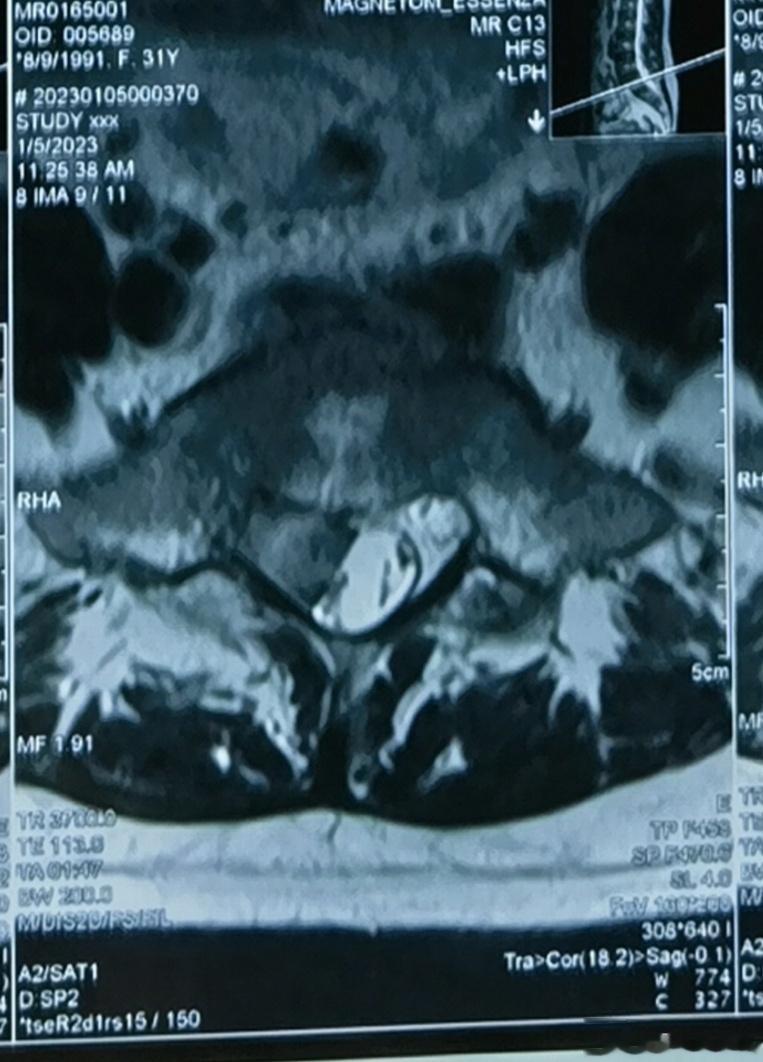

腰椎间盘突出极少导致瘫痪,除非马尾终合征(巨大的椎间盘突出压迫腰椎几乎所有的神经,导致双下肢瘫痪和大小便性功能障碍,需要急诊手术。但是有时候椎间盘突出巨大,也不会导致马尾终合症)。

这个病人的椎间盘突出只是比较大,不至于导致马尾终合症。我没有建议她手术,因为她症状很轻。